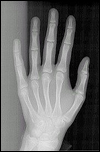

Orthopantomographie (OPG), Orthopantomogramm, Panoramaschichtaufnahme oder Rundumaufnahme aller Zähne (hier sieht man die Nichtanlage von unteren zweiten Prämolaren)